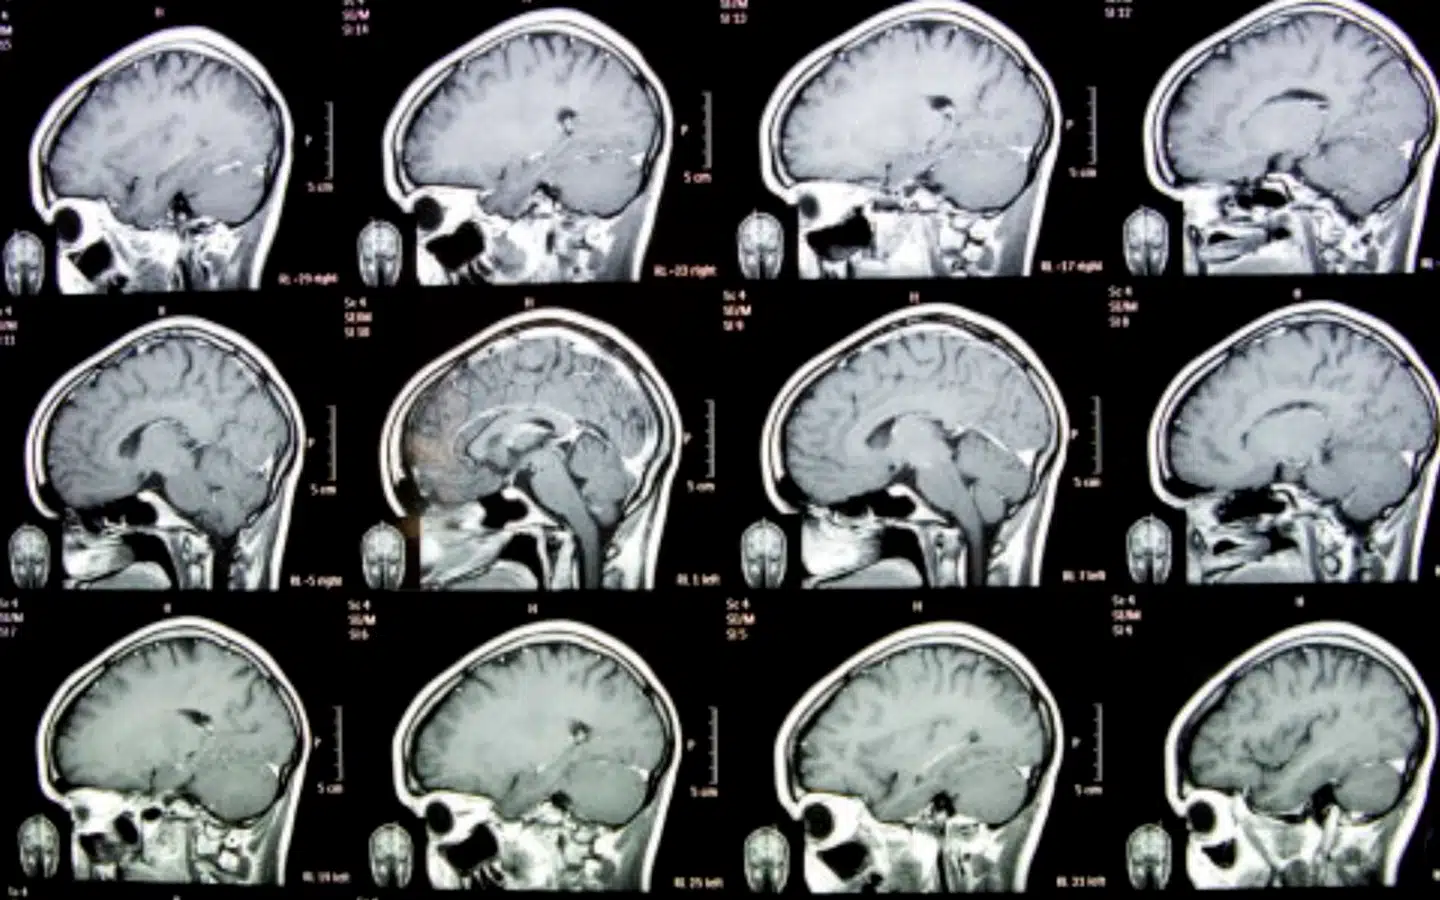

Forskere ved University of Florida oplyser ifølge det amerikanske tidsskrift Inside Precision Medicine, at man har udviklet en vaccine mod kræftformen glioblastom – en aggressiv og hurtigtvoksende form for hjernekræft.

HjernetumorForeningen, der støttes af Kræftens Bekæmpelse, skriver på sin hjemmeside, at den gennemsnitlige overlevelse med hjernekræften er omring 16-20 måneder, og at nogle studier indikerer, at en tumor kan fordoble sin egen størrelse på fire-syv uger.